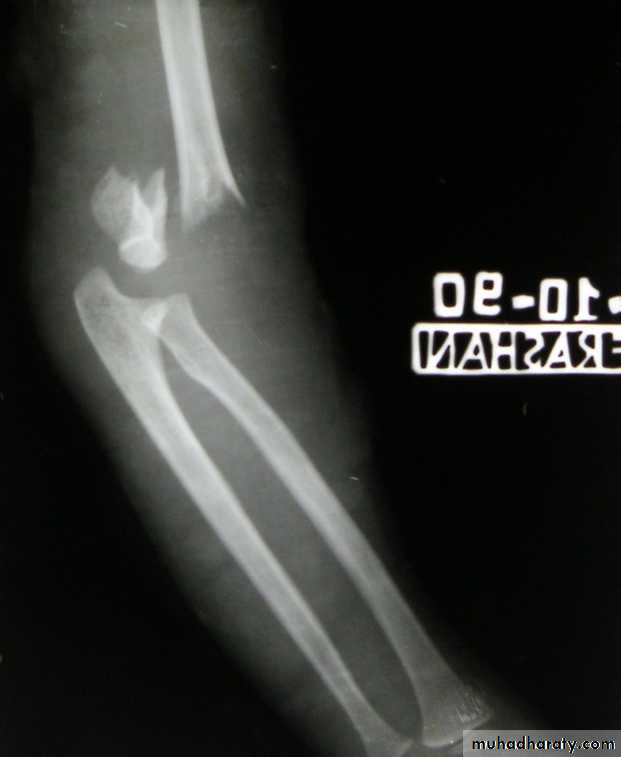

Slide 51-what is the radiological diagnosis?2- what structure in danger in this injury?